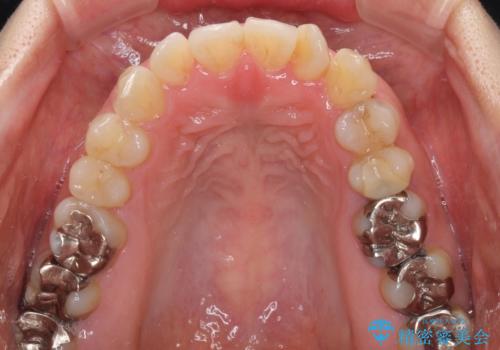

- 前歯の捻れを気にして来院された患者様です。

上顎前歯が捻れて前方に飛び出しており、下顎前歯もそれに沿うようにデコボコとなっていました。

IPR(歯と歯の間を削る処置)によりスペースを獲得して上下前歯のデコボコを改善し、インビザラインにて矯正治療を行うこととしました。

捻れていた前歯の形態が、先端が欠けていたり、一部むし歯処置により左右非対称の形態となっていたため、なかなかゴールが定まらず、治療期間がかかってしまいました。